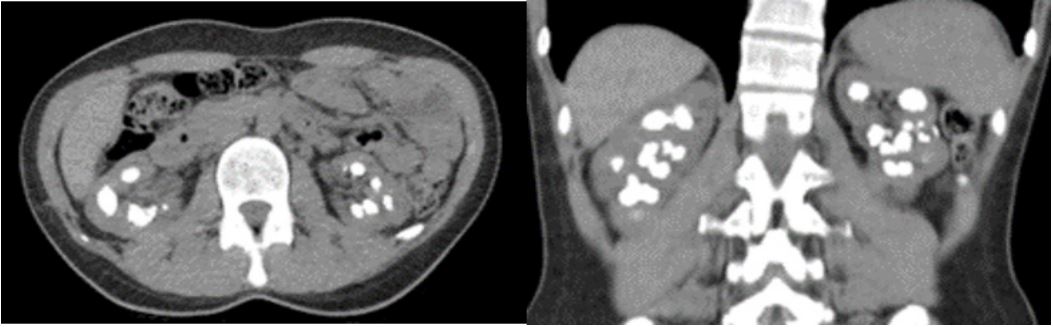

A 38-year-old female patient presented with intermittent bilateral flank pain. She was a first child as a result of consanguineous marriage. She has a hyperparathyroidism and ventricular septum defect. She is followed by nephrology department and cardiology department due to ventral septal defect. She has a previously undergone operation four time left-side percutaneous nephrolithotomy operations, bilateral ureterorenoscopy also bilateral retrograde intrarenal surgery operations. In the Dimercapto Succinic Acid (DMSA) taken on the patient, it was seen that the left kidney was functioning at 39% and the right kidney was functioning at 61%. The patient’s magnesium values were below the normal limit value, and the creatine value was 1.2 mg/dL on average (Figure 2). Other laboratory investigations serum creatinine 1,23 mg/dL, serum urea 31 mg/dL, serum uric acid 6,1 mg/dL, sodium 143 mmol/L, potassium 4,5 mmol/L, calcium 9,2 mg/dL, phosphorus 1,3 mg/dL (below normal range). The results of 24-h urine tests were as follows: magnesium 121,31 mg/day, calcium 263,57 mg/day, oxalate 115,06 mg/day (normal range 4-31), citrate 162,68 mg/day (normal range 320-1260), uric acid 365,8 mg/day. The patient had previously used Potassium Citrate and Thiazide group drugs. Computer tomography taken at her last admission showed multiple stones filling the bilateral kidneys (Figure 1).

Figure 1: CT show a bilateral kidney stones.